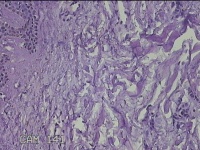

左面部赘生物

性别

男

年龄

47岁

临床诊断

纤维瘤;皮肤感染

一般病史

面部皮肤起赘生物8年。

标本名称

大体所见

灰白粉红色肿物1.3x1.2x0.3cm一个,表面光滑,肿物表面有少许毛发,切面灰白粉红色,质软。

图2